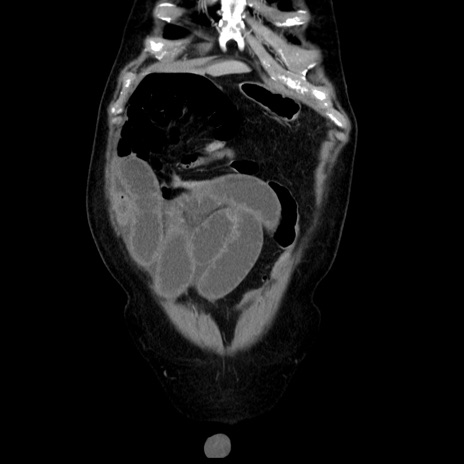

症例30(冠状断像)

【症例】80歳代男性

【主訴】臍周囲痛

【現病歴】約6時間前から臍下部痛が出現。次第に腹部膨隆・背部痛も生じてきたため来院。背部痛の場所は変化しない。

【身体所見】意識清明、BT 36.3℃、BP  131/87mmHg、P 87bpm、SpO2 100%(RA)、臍周囲自発痛・圧痛あり、反跳痛なし、自発痛部位に一致して板状硬あり、腹部膨隆、腸雑音減弱、CVA tenderness両側陰性。